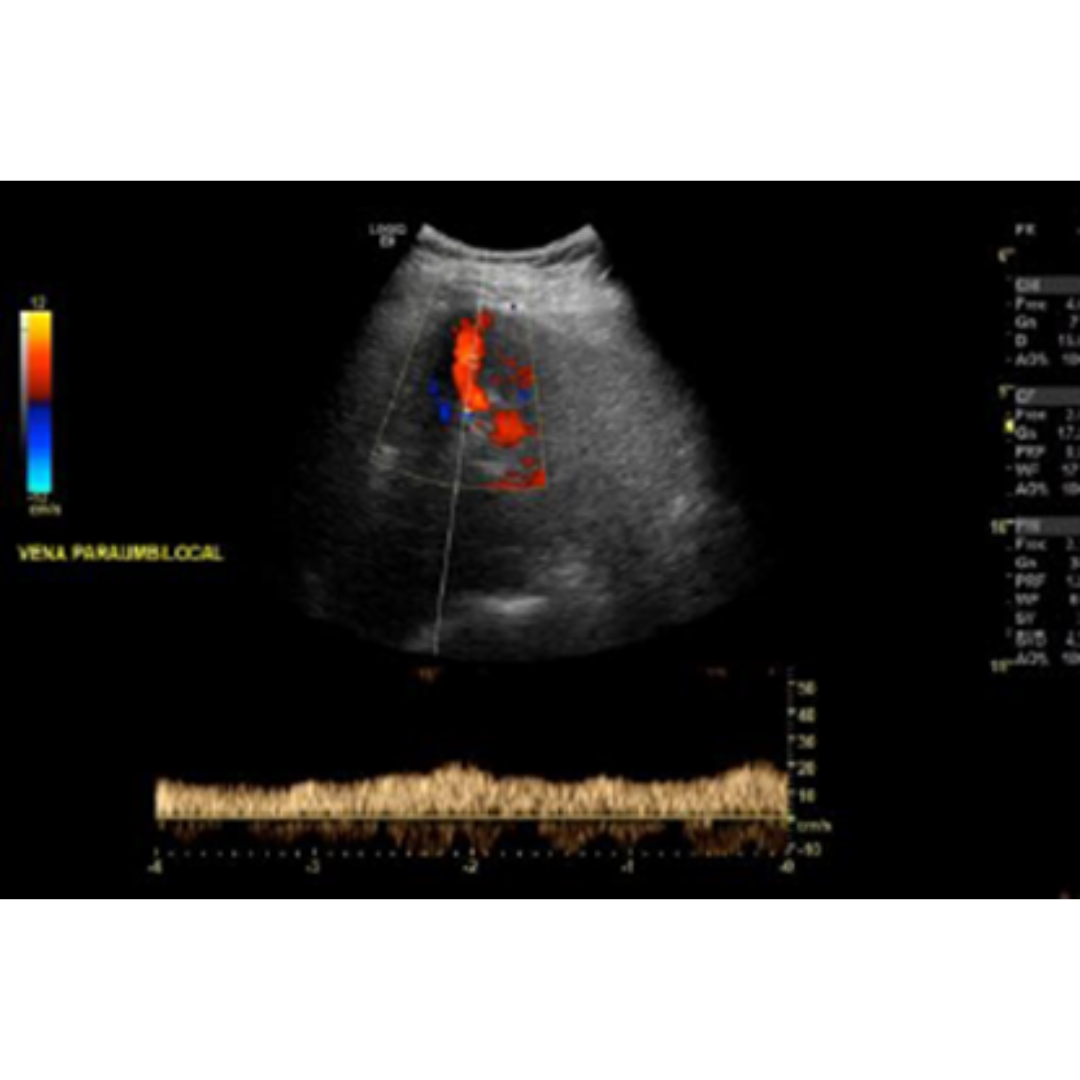

La velocidad portal normal es 15 a 18 cm/s, con el desarrollo de la HP la velocidad disminuye bajo 15 cm/s (figura 7). Las velocidades se verán alteradas por el tipo de colaterales que tenga el paciente. La velocidad media se puede ver aumentada solo en pacientes que presentan recanalización de la vena para umbilical (figura 5-6) y disminuida en pacientes con colaterales espleno-renales (2).

Figura 5-6: Vena porta con flujo hepatopeto, con un estudio espectral con velocidad encima de 25 cm/s, figura 5 paciente con recanalización de vena paraumbilical en paciente con HP severa.

Figura 12: Permeabilización de vena para umbilical con flujo hepatofugo y pico de velocidad de hasta 20 cm/s. Estas venas con flujo hepatofugo alto evitan el desarrollo de varices esofágicas.